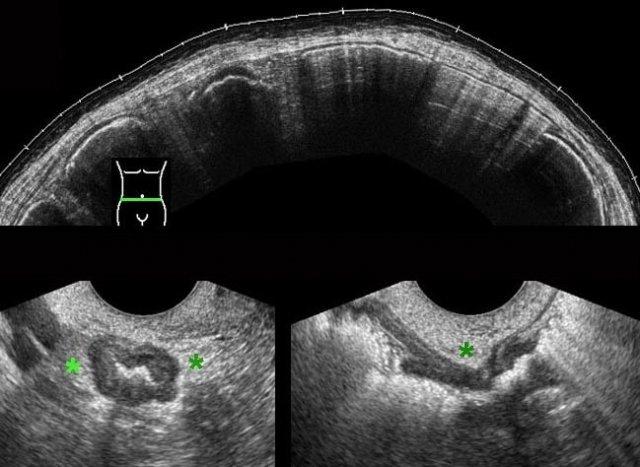

Ở bệnh nhân nữ béo phì, mang thai 3 tuần này, siêu âm qua thành bụng chỉ hiển thị được ruột thừa với hình ảnh nghi ngờ bất thường (← ?).

TVUS cho thấy ruột thừa giãn to, chứa đầy mủ, đang trong tình trạng viêm, nằm ở vị trí sâu trong vùng chậu.